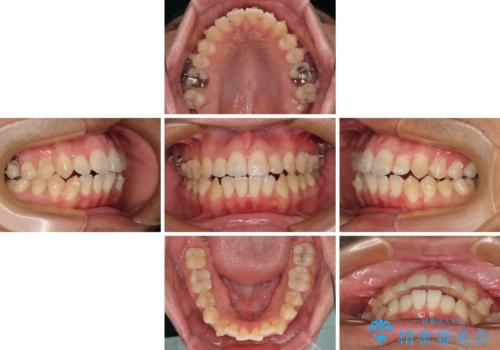

開咬とデコボコを整える インビザライン矯正治療

- 前歯の開咬と叢生を気にして来院された患者様です。

開咬の治療は、前歯を閉じるように動かすとともに、上下臼歯を圧下(骨内にめり込ませる)させることで進めて行きます。

インビザラインは臼歯の圧下を効果的に行えるため、インビザラインを用いて矯正治療を行うこととしました。また、アンカースクリューを用いて、口元の突出感の改善を図りました。

オープンバイトは舌の突出癖により誘発され、治療後も突出癖が残っている容易に後戻りしてしまいます。

治療期間を短縮するためにも、舌突出癖の改善が極めて重要となります。